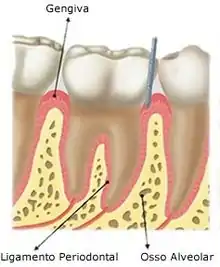

A arcada alveolar é contido de osso alveolar que reveste os alvéolos. Ele é composto de uma fina lâmina de osso cortical, com numerosas perfurações, que permitem a passagem de vasos sanguíneos entre os espaços medulares do osso e ligamento periodontal. A margem coronal do osso alveolar forma a crista alveolar, que geralmente está paralela à junção cemento-esmalte em uma distância de 1-2 mm para apical. O processo alveolar é o maior responsável pelo crescimento vertical da maxila, onde a maior deposição óssea ocorre no seu bordo inferior.

Osso fasciculado (lâmina dura)

- Reveste a parede do alvéolo e pode ser chamado de placa cribiforme

- As partes das fibras colágenas que se inserem nele são denominadas de fibras de Sharpey.